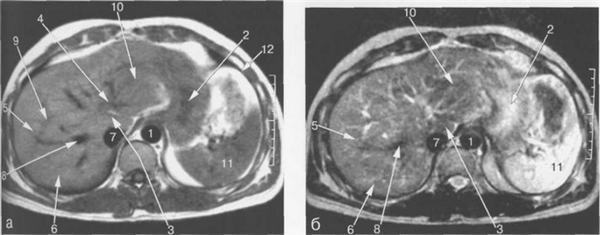

Рис. 11.12. МРТ брюшной полости в аксиальной плоскости на уровне поджелудочной железы.

1 — аорта; 2 — нижняя полая вена; 3 — селезеночная вена; 4 — хвост поджелудочной железы; 5 — желудок; 6 — селезенка; 7 — толстая кишка; 8 — задние сегменты правой доли печени; 9 — задние сегменты ветви правой воротной вены; 10 — передние сегменты ветви правой воротной вены; 11 — медиальные сегменты левой доли печени; 12 — латеральные сегменты левой доли печени; 13 — левый надпочечник; 14 — верхний полюс левой почки.

Рис. 11.13. МРТ брюшной полости в аксиальной плоскости на уровне внутрипеченочных ветвей воротной вены.

1 — аорта; 2 — нижняя полая вена; 3 — селезеночная вена; 4 — тело поджелудочной железы; 5 — желудок; 6 — селезенка; 7 — левый надпочечник; 8 — правый надпочечник; 9 — задние сегменты ветви правой воротной вены; 10 — медиальные сегменты левой доли печени; 11 — верхний полюс левой почки.

Правая печеночная вена расположена в правой межсегментарной борозде, которая отделяет друг от друга передние и задние сегменты правой доли печени (рис. 11.12, 11.13). Левая печеночная вена располагается в левой межсегментарной борозде и разделяет внутренний и наружный сегменты левой доли печени (см. рис. 11.9). Серповидная связка также может использоваться в качестве ориентира, разделяющего внутренний и наружный сегменты левой доли печени.

Хвостатая доля печени располагается кзади и кнаружи относительно нижней полой вены (см. рис. 11.12). Кровоснабжение хвостатой доли осуществляется ветвями как правой, так и левой печеночных артерий и воротной вены. Венозный дренаж происходит в НПВ.

Паренхима печени имеет короткое время релаксации на Т1- и Т2-ВИ. На Т1-ВИ неизмененная печеночная ткань характеризуется средней интенсивностью сигнала, схожей с таковой поджелудочной железы, но более высокой интенсивностью по сравнению с сигналом коркового вещества почек, селезенки и мышц.

На Т2-ВИ паренхима печени характеризуется низкой интенсивностью сигнала, которая соответствует таковой мышц, схожей или более низкой по сравнению с интенсивностью сигнала поджелудочной железы, и значительно более низкой интенсивностью сигнала по сравнению с селезенкой и почками (рис. 11.14—11.16). На Т1- и Т2-ВИ печень имеет однородную структуру.